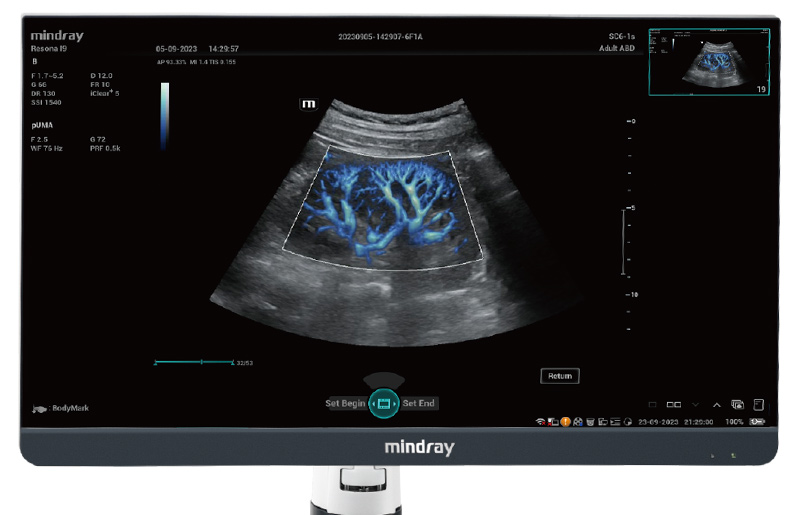

Com tecnologia ZST+

A plataformaZST+ representa um salto extraordinĂĄrio na tecnologia de ultrassom, passando da tradicional forma??o de feixe para o processamento de dados de canal. Essa inova??o revolucionĂĄria supera as compensa??es tradicionais entre resolu??o espacial, resolu??o temporal e uniformidade do tecido, resultando em uma qualidade de imagem inigualĂĄvel com infinitas solu??es de gera??o de imagens.

O Resona I9 fornece solu??es clĂnicas abrangentes para aplica??es dedicadas. Com base em percep??es aprofundadas em diferentes cenĂĄrios clĂnicos, ele oferece inova??es que fornecem aos usuĂĄrios extrema clareza, inteligĂȘncia excepcional e confian?a excepcional no diagnĂłstico.